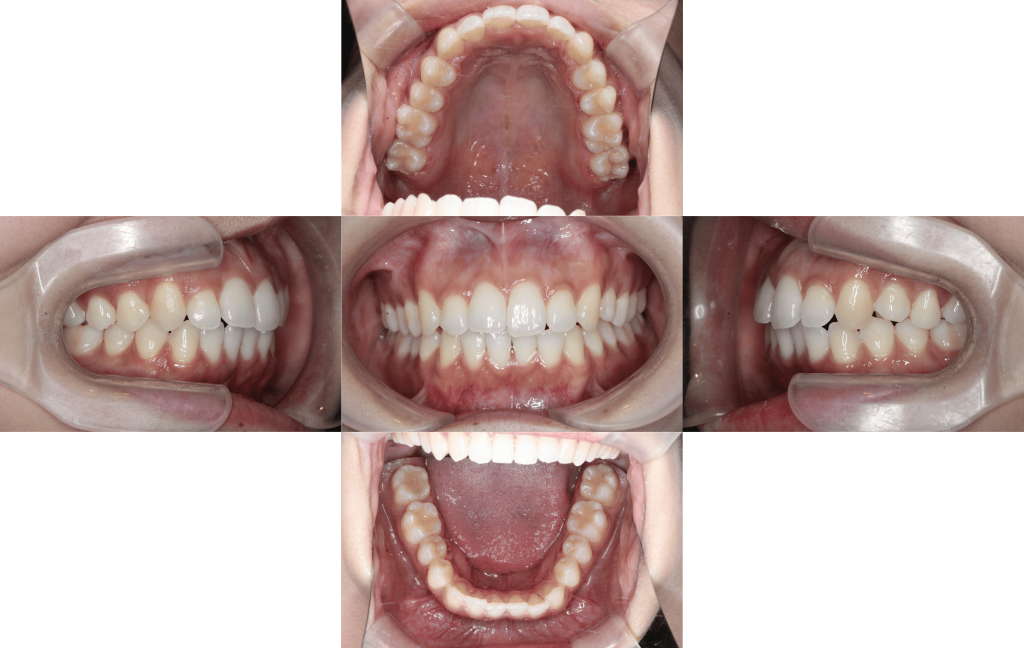

約6か月経過